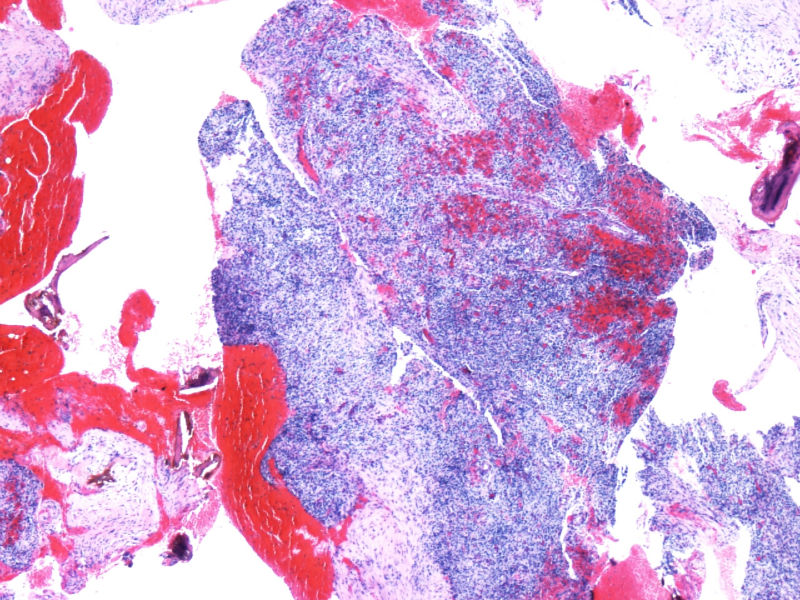

最终诊断为:ALK阳性的间变性大细胞淋巴瘤,淋巴组织细胞变异型。

拿出来的目的:本例始发于骨骼,临床提示脓肿或骨髓瘤,ALK阳性但EMA阴性,细胞毒只有一个标记阳性,本例CD4不阳性。因为CD30和CD15均有非肿瘤细胞阳性的情况,所以对于这个骨骼病例,细胞少而退变,因此最初没有信心诊断,但ALK一般不在非肿瘤细胞内阳性表达,所以最终还是诊断了ALCL。

此病例是非常特殊,其表现为:

1)ALCL很少原发于骨组织,

2)肿瘤细胞免疫表型特殊, CD30+CD15+ALK-1+CD43+Perforin+, 而其他PanB细胞和PanT细胞的标记均为阴性。

3)楼主诊断ALCL主要根据是 ALK-1+, 很有说服力!